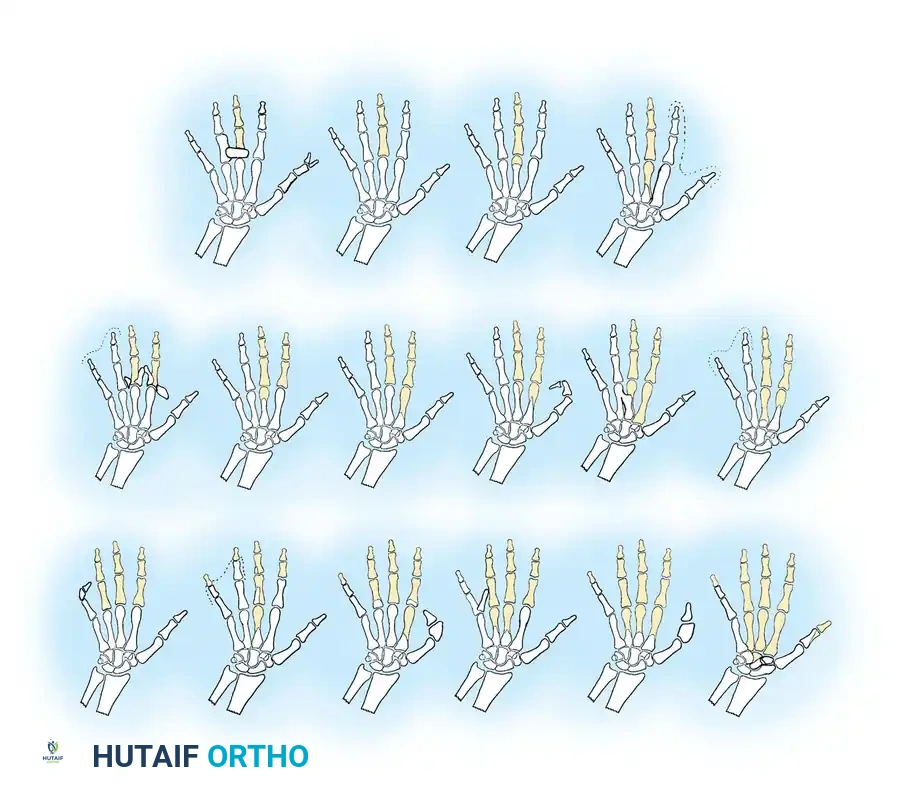

Failure of Formation: Transverse Deficiencies

Transverse deficiencies represent a failure of formation (arrest of development) characterized by the complete absence of parts distal to a specific point on the upper extremity. This produces an amputation-like stump. Classification is strictly anatomical, naming the level at which the remaining stump terminates (e.g., proximal third forearm deficiency).

While transverse deficiencies typically occur as isolated anomalies, they have been reported in association with several malformation syndromes and conditions, including:

* Hydrocephalus

* Spina bifida and myelomeningocele

* Congenital talipes equinovarus (Clubfoot)

* Radial head dislocation

* Radioulnar synostosis